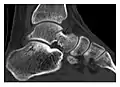

The greater tuberosity of the humerus is also an illustrative location of occult fractures. The osseous injury may follow seizures, glenohumeral dislocation, forced abduction, or direct impaction. They are commonly discovered on MRI in symptomatic patients with suspicion of rotator cuff tear. Coronal images are best suited for detection. They appear as crescentic oblique lines surrounded by a bone marrow edema pattern (Figure 5). The rotator cuff must be inspected since associated ligamentous lesions are common. In the ankle, malleoli and tarsal bones should be checked carefully for any cortical disruptions and radiolucent lines that may reveal a fracture. Awareness of the exact location of the pain will help direct the attention of the interpreter when searching for very subtle signs of fracture (Figure 6).[1]

a

b

Figure 6: Subtle anterior talar fracture in a 39-year-old man presenting with ankle pain after a fall. (a) Anteroposterior radiograph shows a subtle oblique radiolucent line through the talus (white arrows). (b) Sagittal CT reformation confirms the presence of an anterior talar fracture with cortical offset (black arrow). Avulsion fractures, which consist of a detached bone fragment resulting from a ligament or tendon pulling away from the bone, may also present with subtle radiographic signs. Tiny osseous fragments near the presumed attachment site of a ligament suggest this diagnosis. Common sites are the lateral tibial plateau (the Segond fracture), the spinal tuberosity of the tibia resulting from anterior cruciate ligament avulsion, and the ischial tuberosity.[1]